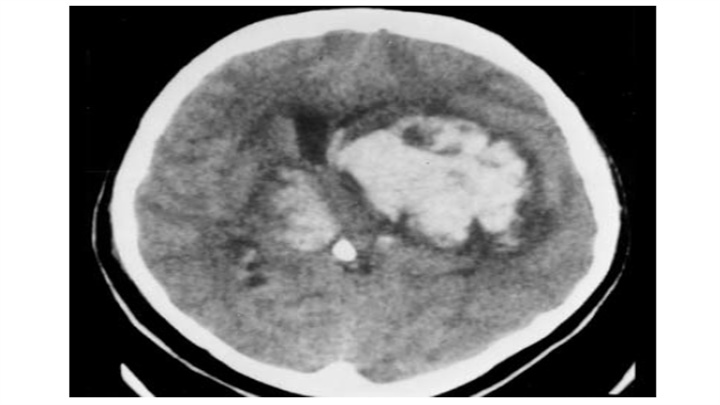

大量脑出血,累及左丘脑和基底节。明显的占位效应(中线结构向对侧明显移位)和脑室积血(同侧脑室变扁,右侧枕角积血)。然而,像往常一样,腹周水肿的数量仅限于周围边界。患者在数小时后死亡。